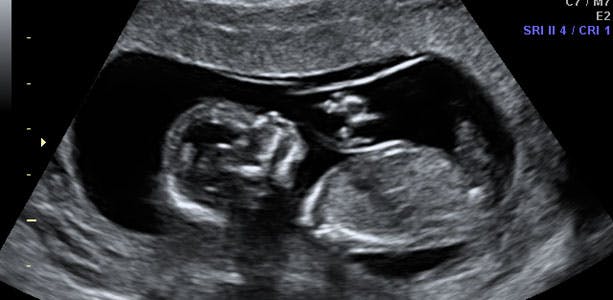

Gravid uge 14: Baby kan gribe og sparke

På dette tidspunkt i din graviditet kan din baby både drikke og tisse, fordi nyrer, urinveje og blæren nu er udviklet. Hænderne kan gribe og de lange ben sparke, men endnu ikke så det kan mærkes. Hvornår du mærker liv afhænger også meget af, hvorledes din moderkage sidder. Sidder den på bagvæggen af livmoderen (ind imod din rygsøjle), vil du mærke liv tidligere, end hvis den sidder på forvæggen (ud imod dit maveskind). I slutningen af ugen måler barnet cirka 13 centimeter og vejer cirka 100 gram.